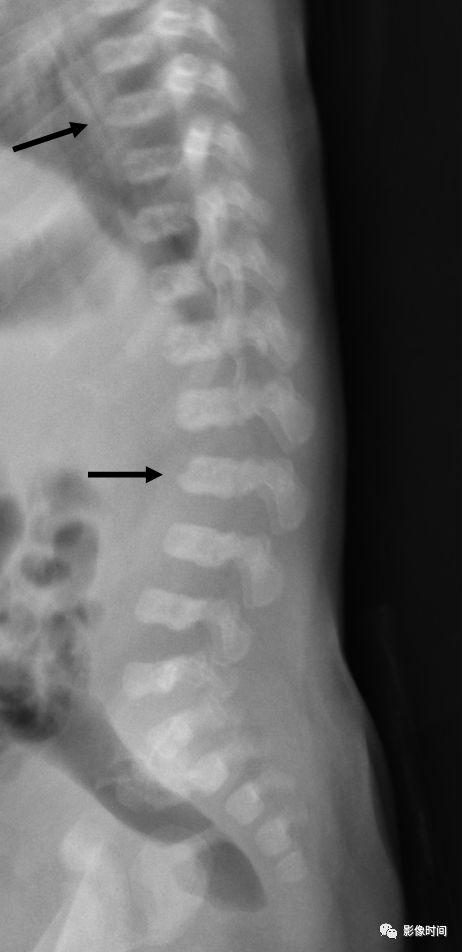

NF1患者脊柱在形态学上的异常主要包括椎体楔形变、椎体扇贝样改变(图6)、椎弓根狭窄(图7)、椎弓根间距增宽、横突纺锤形改变以及椎管扩大等。以上征象很少单独出现,往往合并存在。

图. 男性,14岁,X线下典型的椎体扇贝样改变